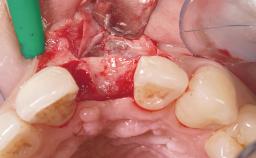

A 42-year-old female patient was referred to our clinic at the School of Dentistry of the University of São Paulo in November 2004, presenting a deficient restoration in the upper left central incisor. The clinical examination revealed no gingival retraction or any signs of gingival inflammation and, therefore, previous periodontal treatment was not considered. The patient presented a high lip line at full smile and a thin tissue biotype. This combination characterized a high-risk situation from an anatomic point of view, which required careful preoperative planning and cautious surgical execution.

Placement Protocol Immediate implant placement

Socket Morphology Single-root socket

Socket Integrity Sufficient, with intact bone walls